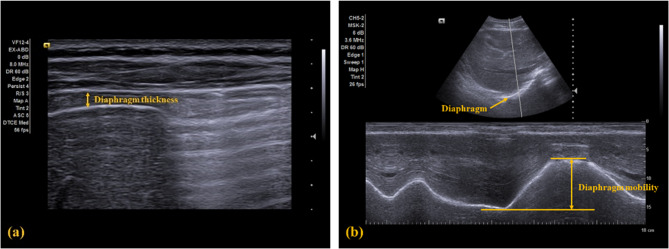

Diaphragm function in this study was indicated as the thickness and mobility of the diaphragm and measured using ultrasonography (ACUSON NX3TM, Siemens Solution, USA, Inc). Diaphragm thickness was captured under the B mode using a 4–12 MHz linear transducer, and diaphragm mobility was recorded under the M mode using a 1–5 MHz curved transducer. Participants were positioned in a 30° semi-recumbent supine position with 90° knee bending, and the right side of the diaphragm was measured [ref. 43, ref. 44]. Five images were recorded for each outcome or condition and then measured using the ImageJ software. The intra-rater reliability for the current study has been examined in a pilot study on 10 young adults and is good to excellent (ICC3,3 = 0.804 to 0.986).

For the diaphragm thickness, the linear transducer was placed between the anterior and medial axillary line at the diaphragm apposition zone, parallel with the rib bones. The images of diaphragm thickness were taken at the end of the maximal inhalation and exhalation (Fig. 3a). Diaphragm thickness was measured as the hypoechoic distance between the hyperechoic pleural and peritoneal lines in millimeters. The diaphragm thickness change between the maximal inspiration and expiration was then calculated. The MCID for the diaphragm thickness measured via ultrasonography in patients with CNP has not yet been established.

For the diaphragm mobility, the curved transducer was placed at the anterior subcostal region on the mid-clavicular line, with the craniocaudal central line passing through the gall bladder. A hyperechoic line indicating the diaphragm was visualized in the ultrasonogram (Fig. 3b). For measuring the mobility, participants were instructed to perform two tidal breaths, followed by a maximal inhalation and exhalation. Diaphragm mobility was defined as the displacement between the highest (i.e., maximal inhalation) and lowest (i.e., maximal exhalation) positions of the diaphragm and recorded in millimeters. The MCID for the diaphragm also has not been established.